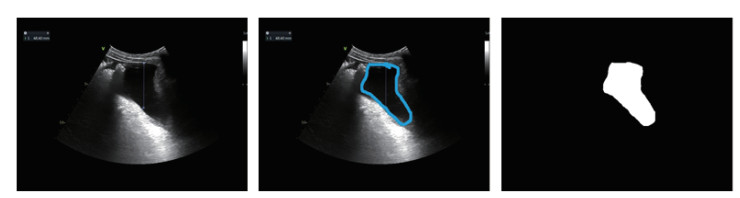

对于每张胸腹部超声出血的原始超声图像(图 1A),由超声科医生标注出血范围标注图像(图 1B),通过比较原始超声图像和标注图像之间的颜色差异,并做二值化,形态学滤波、连通区域提取操作,生成超声出血区域的掩码图像(图 1C),其中白色为出血区域,黑色为背景。

A: 图像B: 标注C: 掩码 图 1 原始超声图像、标注图像和生成的掩码图像